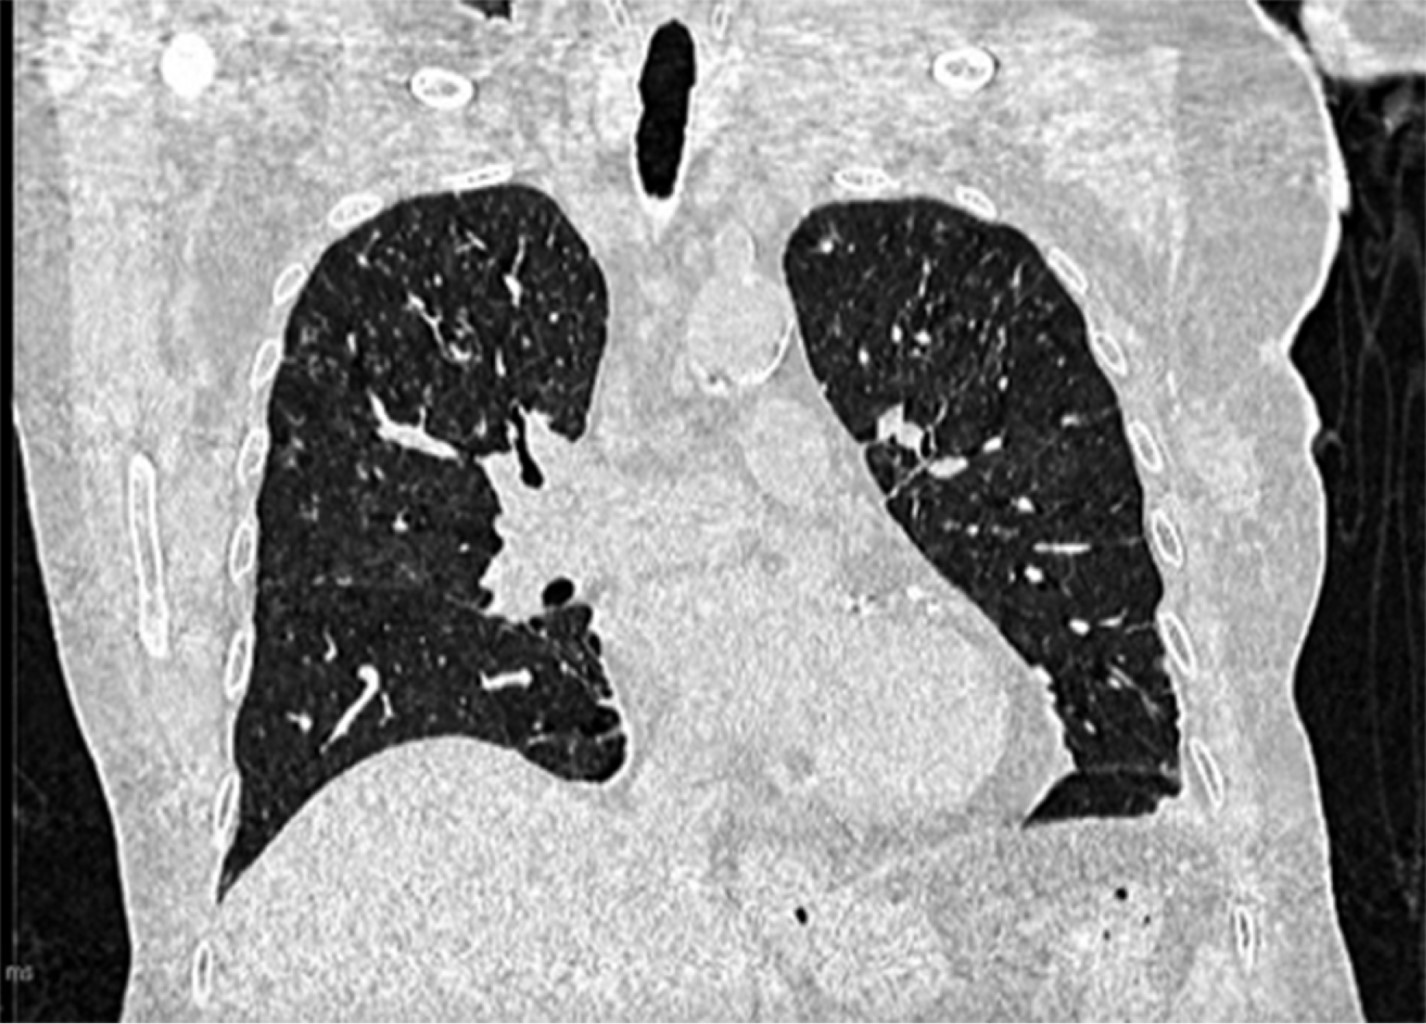

Extrapulmonary tuberculosis ''The great simulator''.

Tuberculosis is an infectious disease considered a public health problem since it is one of the main causes of morbidity and mortality worldwide; the most common clinical form is pulmonary tuberculosis; however, this disease can also affect extrapulmonary structures whose diagnosis is generally late because the symptoms and signs are nonspecific. This article presents a clinical case of extrapulmonary tuberculosis (miliary, central nervous system and intestinal) at the University Hospital of Puebla.

Figure 2